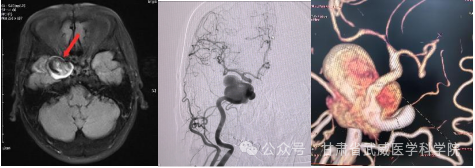

病例介绍:患者程某,女性,62岁,主因“确诊颅内动脉瘤2周”入院,现症:患者头痛、头晕、伴右眼外展活动受限,完善头颅核磁示右侧海绵窦区占位,脑血管造影见右侧颈内动脉海绵窦段可见一大小约32.8mm*27.4mm*5.02mm的动脉瘤。

术前核磁、DSA影像